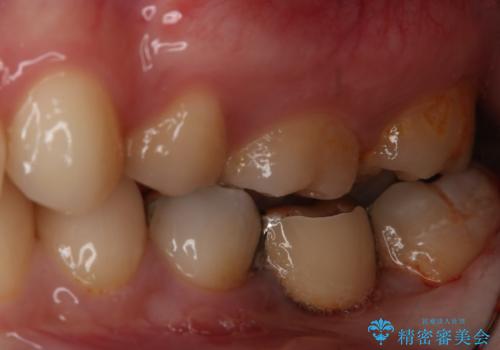

- 左下奥歯のブリッジのやり変え希望のため来院された患者様です。

支台歯部分はインレー形態でしたが強度や維持性を考慮しクラウン形態への変更を計画しました。

患者様の希望によりフルジルコニアブリッジを選択しました。